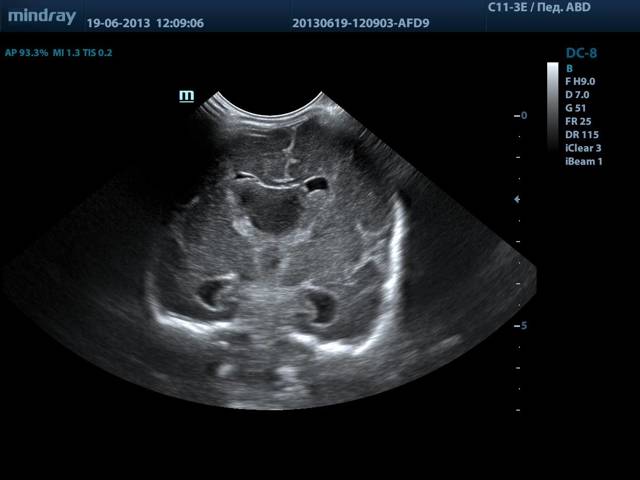

Узи сосудистой системы головного мозга

Если говорить об ультразвуковом исследовании, то с уверенностью можно сказать, что речь идёт о довольно информативном методе оценки состояния кровотока в капиллярах, венах, артериях, которые снабжают кровью головной мозг. УЗИ головы проводят тремя способами:

Как УЗИ головного мозга, так и МРТ используются для оценки состояния сосудов, снабжающих мозг. Исследуются структура сонных артерий и внутренний слой кровеносных сосудов, чтобы вовремя обнаружить обызвествление и атеросклеротические бляшки и начать лечение. Для обследования самого мозга применяются нейросонография (у грудных детей) и транскраниальная сонография.

Ультразвуковое исследование головы позволяет получить изображение мозга и ликвора.

Так как волны плохо проходят сквозь кость, этот метод обычно используют для выявления патологий на ранней стадии у младенцев, череп которых еще не полностью сформирован.

Акустическими окнами у новорожденных служат роднички, то есть мягкие, не окостеневшие участки. Врач приставляет датчик, например, к переднему родничку и водит им вправо и влево, вперед и назад, чтобы как можно точнее визуализировать структуры мозга.